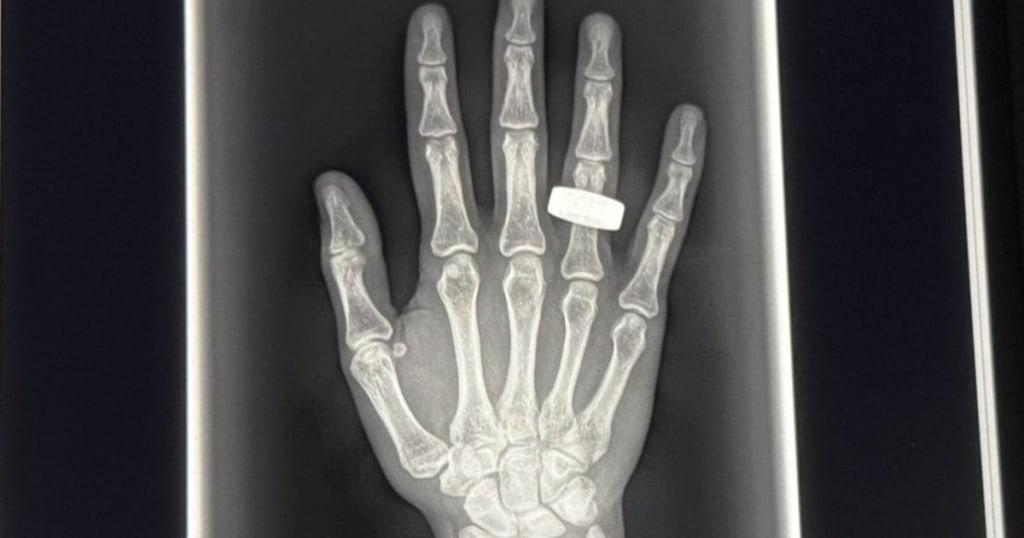

In a groundbreaking milestone for both space exploration and medical science the first ever X-ray images of the human body in space have been captured. This historic achievement marks a significant advancement in our ability to monitor and understand human health during extended missions beyond Earth’s atmosphere. For decades scientists and doctors have speculated about the effects of microgravity on the human body but now thanks to advanced X-ray technology developed specifically for space environments we finally have an inside look quite literally. The images were taken aboard the International Space Station ISS using a compact lightweight X-ray device designed to function in the unique and challenging conditions of microgravity. Unlike traditional X-ray machines which rely on bulky equipment and stable conditions this newly developed technology uses low dose radiation and digital imaging techniques to safely and effectively scan the human body in space. The device was used by astronauts to capture high resolution X-ray images of their own bodies focusing primarily on the chest spine and limbs. These images offer the first direct visual evidence of how bones and internal organs adapt to weightlessness a topic that has intrigued scientists since the beginning of human spaceflight.

X-ray imaging is one of the most essential tools in medical diagnostics on Earth. Being able to apply the same tool in space opens new possibilities for monitoring astronaut health in real time diagnosing injuries and even planning emergency treatments during long missions such as those to Mars or the Moon. One of the primary concerns during extended space missions is bone density loss. In the absence of gravity bones lose calcium and other minerals at a much faster rate than on Earth. While previous studies used indirect methods like ultrasound or CT scans before and after space travel, these new X-ray images provide immediate and highly accurate insights. Moreover real time X-ray capabilities allow doctors on Earth to consult live with astronauts guiding them through diagnostic procedures. This becomes critical in the event of injury or illness far from Earth where medical evacuation is not an option.

The success of space based X-ray imaging comes after years of development and collaboration between space agencies tech companies and medical institutions. NASA in collaboration with private space tech developers, engineered a portable X-ray system that uses less power, emits lower radiation levels and operates efficiently in zero gravity. The system includes advanced AI software that assists astronauts in taking the correct scans analyzing image quality and even performing preliminary diagnoses. It’s a true example of the fusion between artificial intelligence medical science and aerospace engineering. With the success of this pilot test aboard the ISS space agencies are now considering making X-ray imaging a standard part of medical kits for all future crewed missions. Whether it’s a journey to the Moon under NASA’s Artemis program or the ambitious Mars missions planned for the 2030s having real time medical imaging on board will be crucial for the safety and survival of astronauts. Additionally the technology could pave the way for telemedicine in extreme environments not just in space but also in remote areas on Earth where access to medical imaging is limited. The first X-ray images of the human body in space are more than just medical pictures they are a giant leap forward in the evolution of space medicine. As humanity prepares to venture further into the cosmos tools like these will play a pivotal role in ensuring that we can not only survive but thrive beyond our home planet. This historic moment is a testament to human ingenuity and the unending pursuit of knowledge proving once again that science has no boundaries even in space.